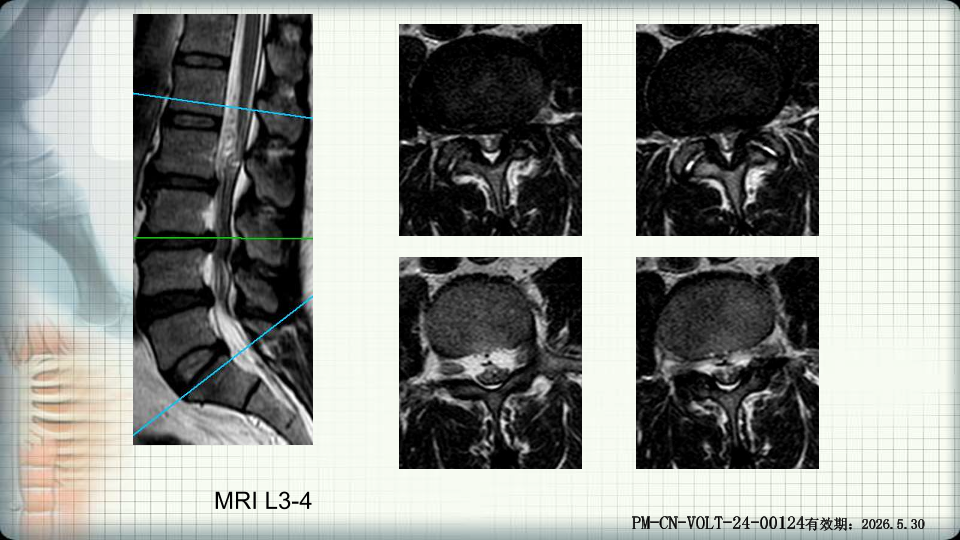

管狭窄症非手术治疗-谢学虎